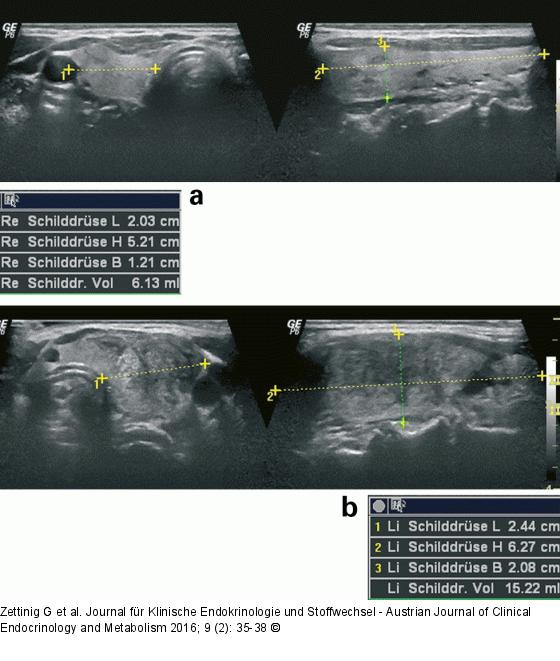

Abbildung 1a-b: Subakute Thyreoiditis 56-jährige Patientin mit subakuter Thyreoiditis im linken Lappen. 1a: Der rechte Schilddrüsenlappen zeigt lediglich einzelne degenerative Veränderungen und kleine echoarme Umbauzonen (links Querschnitt, rechts Längsschnitt). 1b: Der linke Lappen ist mit 15 ml deutlich vergrößert und zeigt inmitten des normalen Schilddrüsenparenchyms zahlreiche echoarme, landkartenartig konfigurierte echoarme Areale (links Querschnitt, rechts Längsschnitt). |

56-jährige Patientin mit subakuter Thyreoiditis im linken Lappen. 1a: Der rechte Schilddrüsenlappen zeigt lediglich einzelne degenerative Veränderungen und kleine echoarme Umbauzonen (links Querschnitt, rechts Längsschnitt). 1b: Der linke Lappen ist mit 15 ml deutlich vergrößert und zeigt inmitten des normalen Schilddrüsenparenchyms zahlreiche echoarme, landkartenartig konfigurierte echoarme Areale (links Querschnitt, rechts Längsschnitt). |